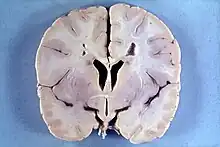

Many people with abnormally large heads or large skulls are healthy, but macrocephaly may be pathological. Pathologic macrocephaly may be due to megalencephaly (enlarged brain), hydrocephalus (abnormally increased cerebrospinal fluid), cranial hyperostosis (bone overgrowth), and other conditions. Pathologic macrocephaly is called "syndromic", when it is associated with any other noteworthy condition, and "nonsyndromic" otherwise. Pathologic macrocephaly may be caused by congenital anatomic abnormalities, genetic conditions, or by environmental events.[2]

In research, cranial height or brain imaging may be used to determine intracranial volume more accurately.[2]